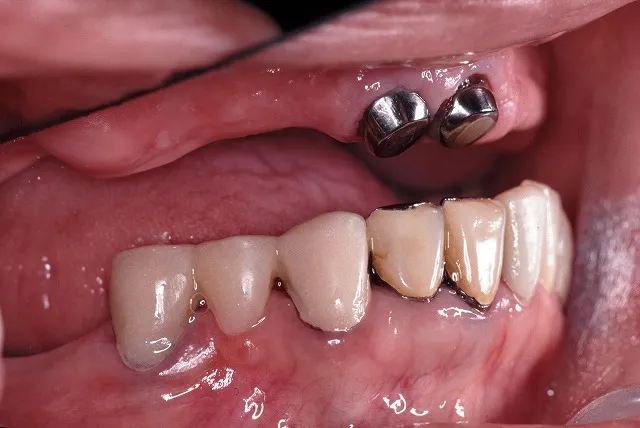

■治療後